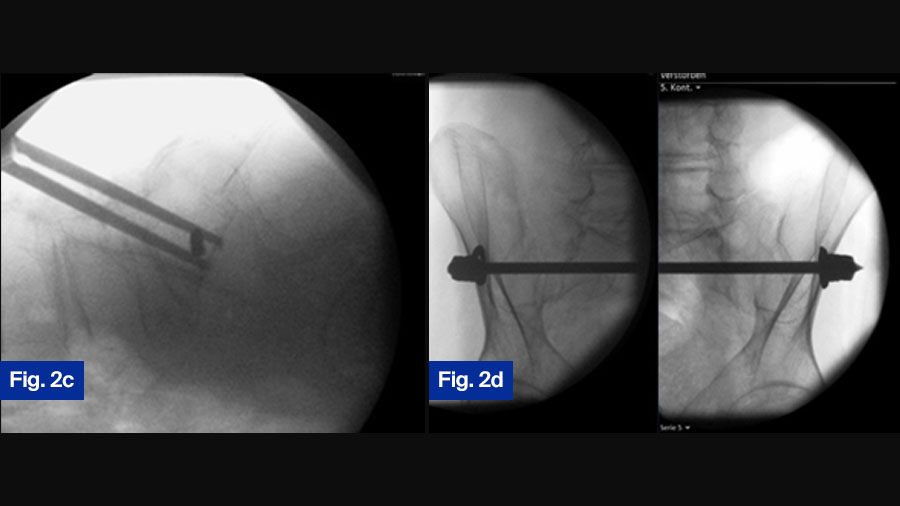

Case Study 2: 92-year-old female with bilateral sacral fracture (FFP Type IVb)

Figure 2. 92-year-old female patient presenting 1 week after fall from standing height with immobilizing pain at lower lumbar spine. (a) Axial CT demonstrating slight displacement of bilateral sacral fracture; (b) sagittal CT with displaced transversal fracture at S1/S2 level. The fracture was classified as FFP type IVb. (c) Lateral fluoroscopic image orientated in direction of the patient (bottom anterior, left cranial) showing overlapping of ilio-cortical densities and ischial notch.

The drill guide is placed centrally in S1 corridor caudal to the ilio-cortical densities. (d) Oblique obturator view to assess the abutment of the washer on the iliac cortex.

Postoperative control at discharge, patient is mobile with a walker ( (e) anterior–posterior, (f) inlet, and (g) outlet view ).